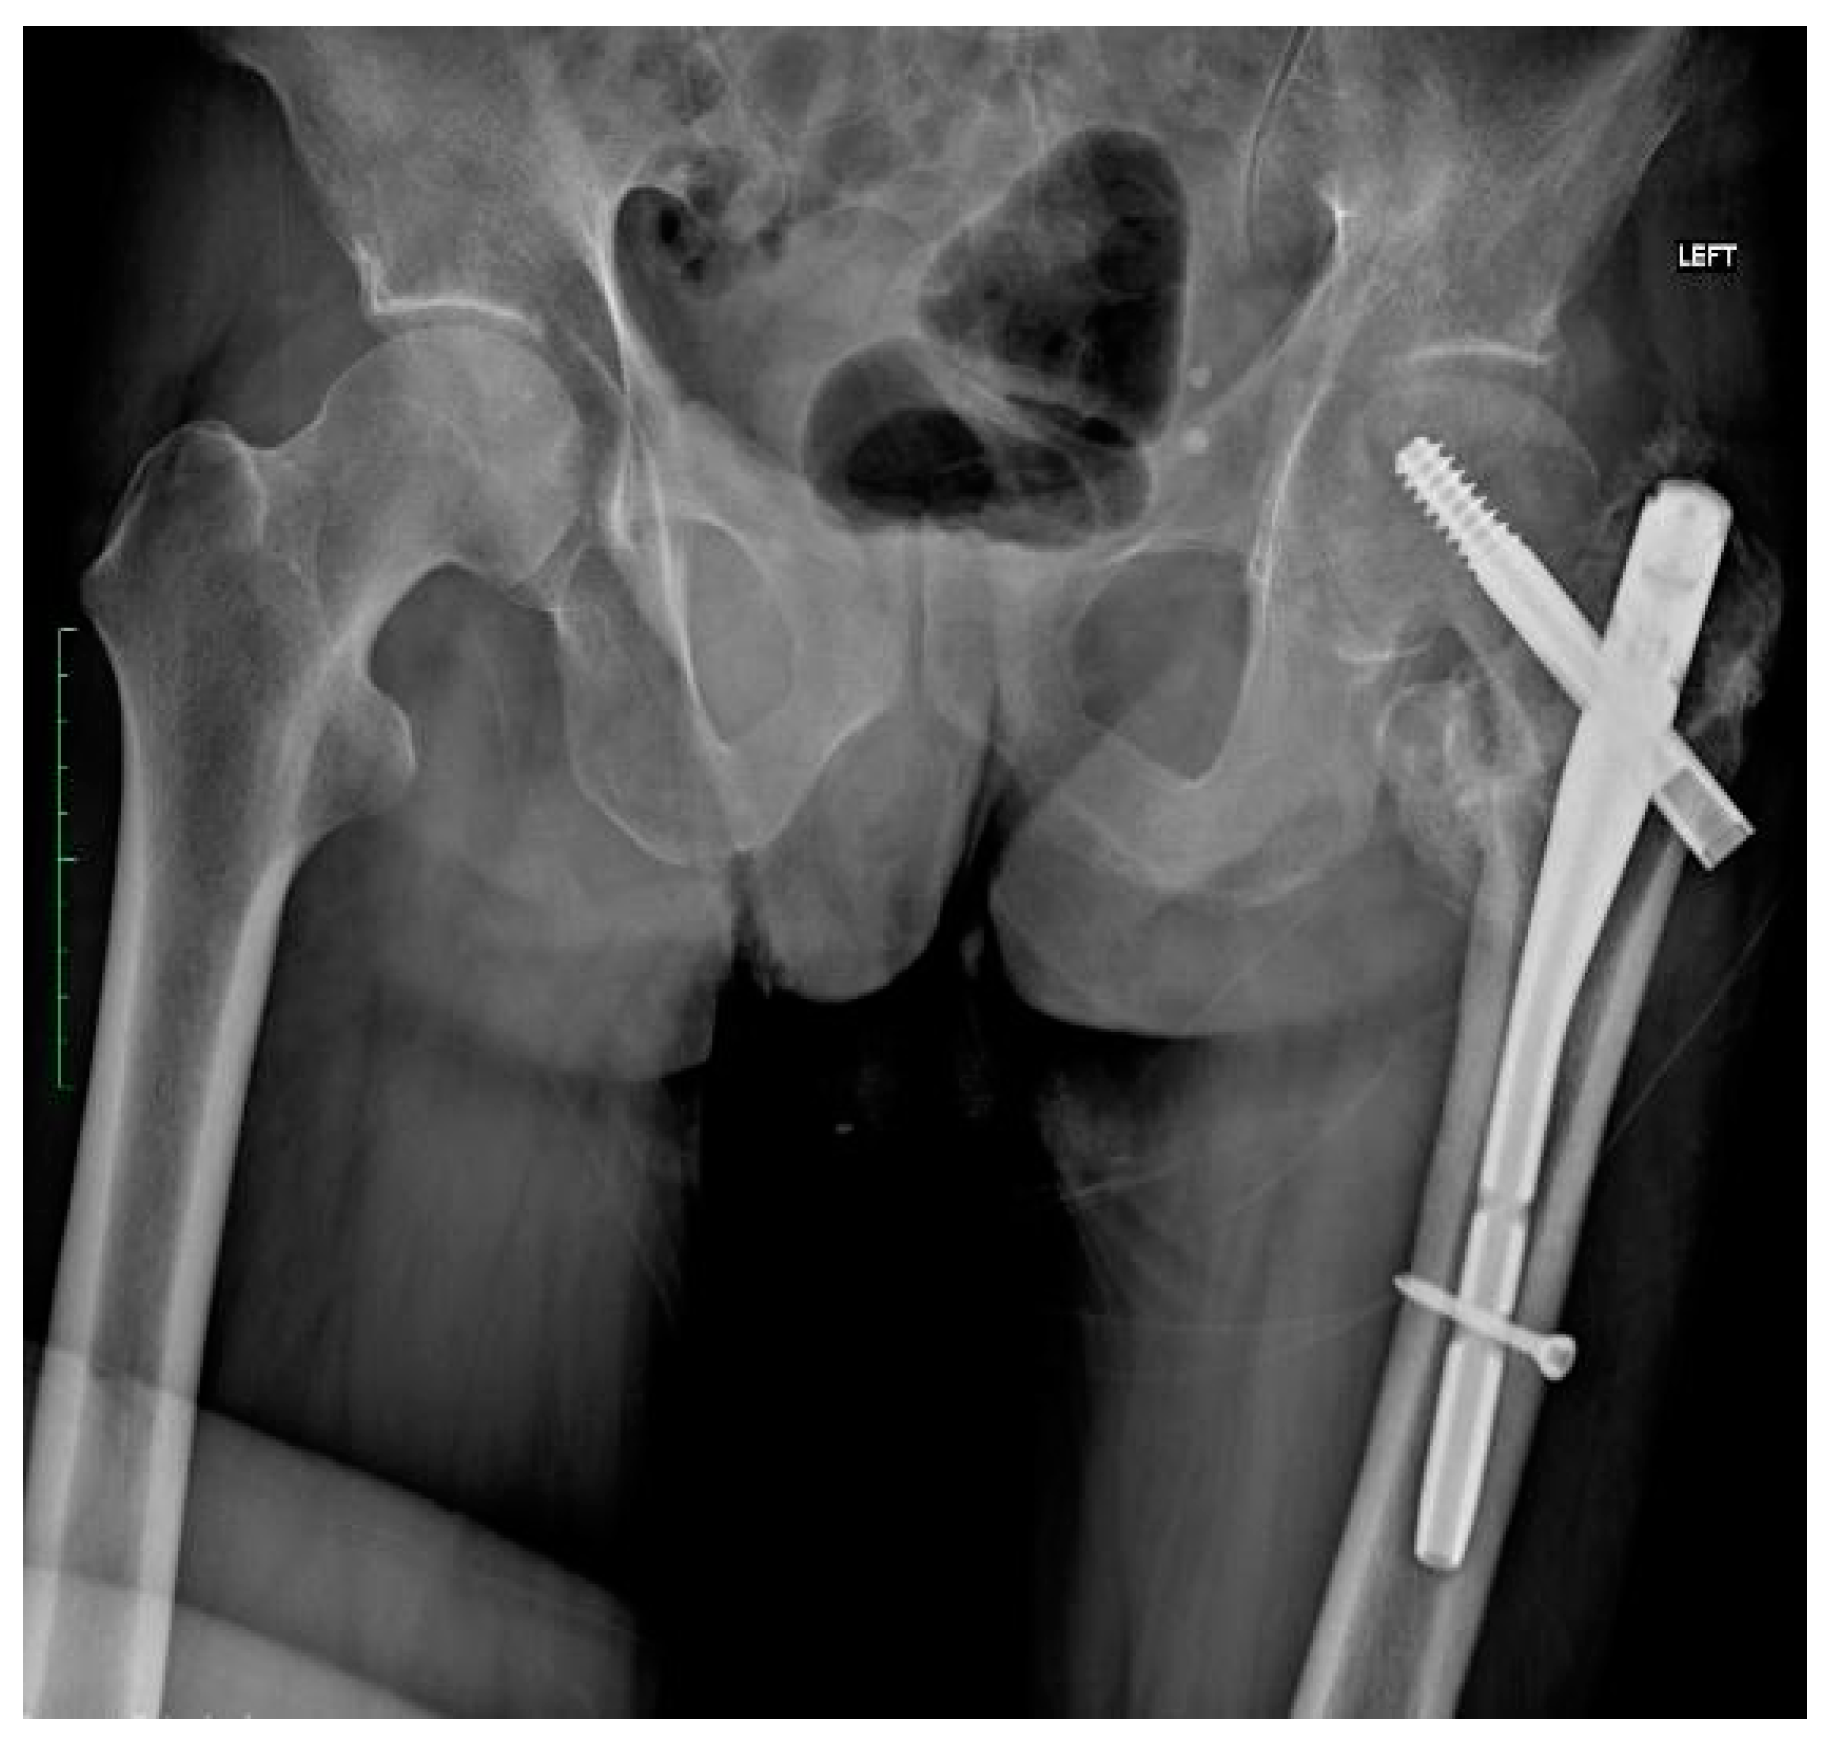

2.3. Initial Treatment

2.4. Fracture and Initial Surgery

| First Stage of Treatment—January 2023 Removal of the failed fixation, filing the bone defects with calcium sulphate antibiotic carrier | ||